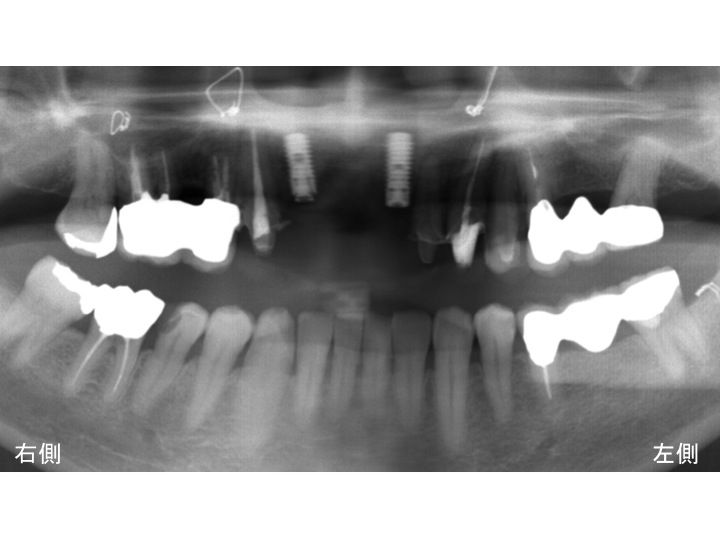

抜歯後に3回に分けて奥歯にインプラントを埋入しました。

以下がインプラント手術後のレントゲン写真です。